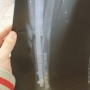

이거 과실이 얼마나 되나요? 8:2라고 보험사에서 그러는데,,ㅠㅠ